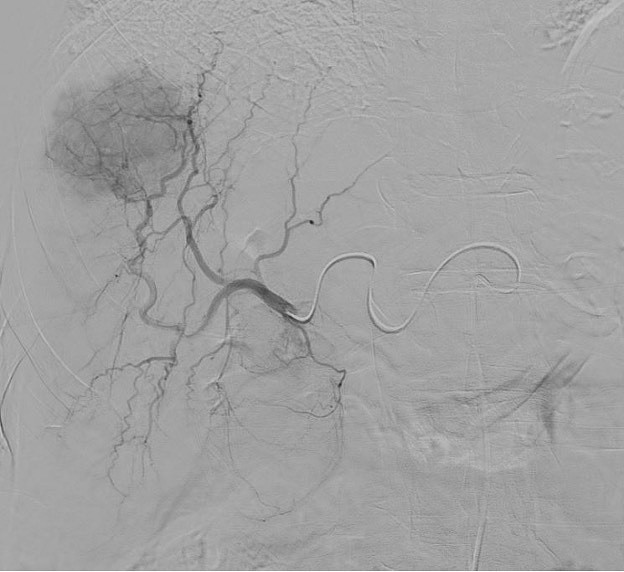

Equipped with sophisticated advanced image-guidance systems and multi-imaging modalities, our physicians may now better visualize and treat patients with complicated diseases. This system includes technology to make this easier in both 2D and 3D with dose reduction technology. It is equipped with integrated Intravascular Ultrasound. Vessel Navigation guidance, 2D Vessel Perfusion, 3D roadmap and Vessel quantitative measurements are offered as well. Vessel Navigator allows reuse of 3D vascular anatomical information from existing CTA and MRA datasets as a 3D roadmap overlay on live X-ray images. With its sophisticated visualization, it provides an intuitive and continuous 3D roadmap to guide you through vasculature during the entire procedure. The system is connected to our PACS system allowing us to visualize previous diagnostic images inside the room.

Stephan Wicky van Doyer, MD: “The performance, technology and quality of the new angio suite is absolutely fantastic. The room size allows multiple providers to feel comfortable and safe. It allows us to perform very challenging procedures in a safe and secure environment for the patient benefit. Different imaging guidance systems such as IVUS and Navigation, shorten the duration of the procedure and our patients also are exposed to a much lower radiation dose.”